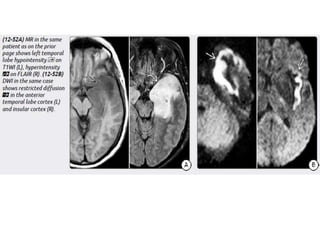

Imaging

NECT scans may be normal or show a hypodense extraaxial collection

that demonstrates peripheral enhancement on CECT.

Bone CT should be evaluated for signs of sinusitis and otomastoiditis.

MR is the procedure of choice for evaluating potential empyemas. T1

scans show an extraaxial collection that is mildly hyperintense relative to

CSF.

SDEs are typically crescentic and lie over the cerebral hemisphere. SDEs

often extend into the interhemispheric fissure but do not cross the midline.

EDEs are biconvex and usually more focal than SDEs. EDEs may cross

the midline, confirming their epidural location